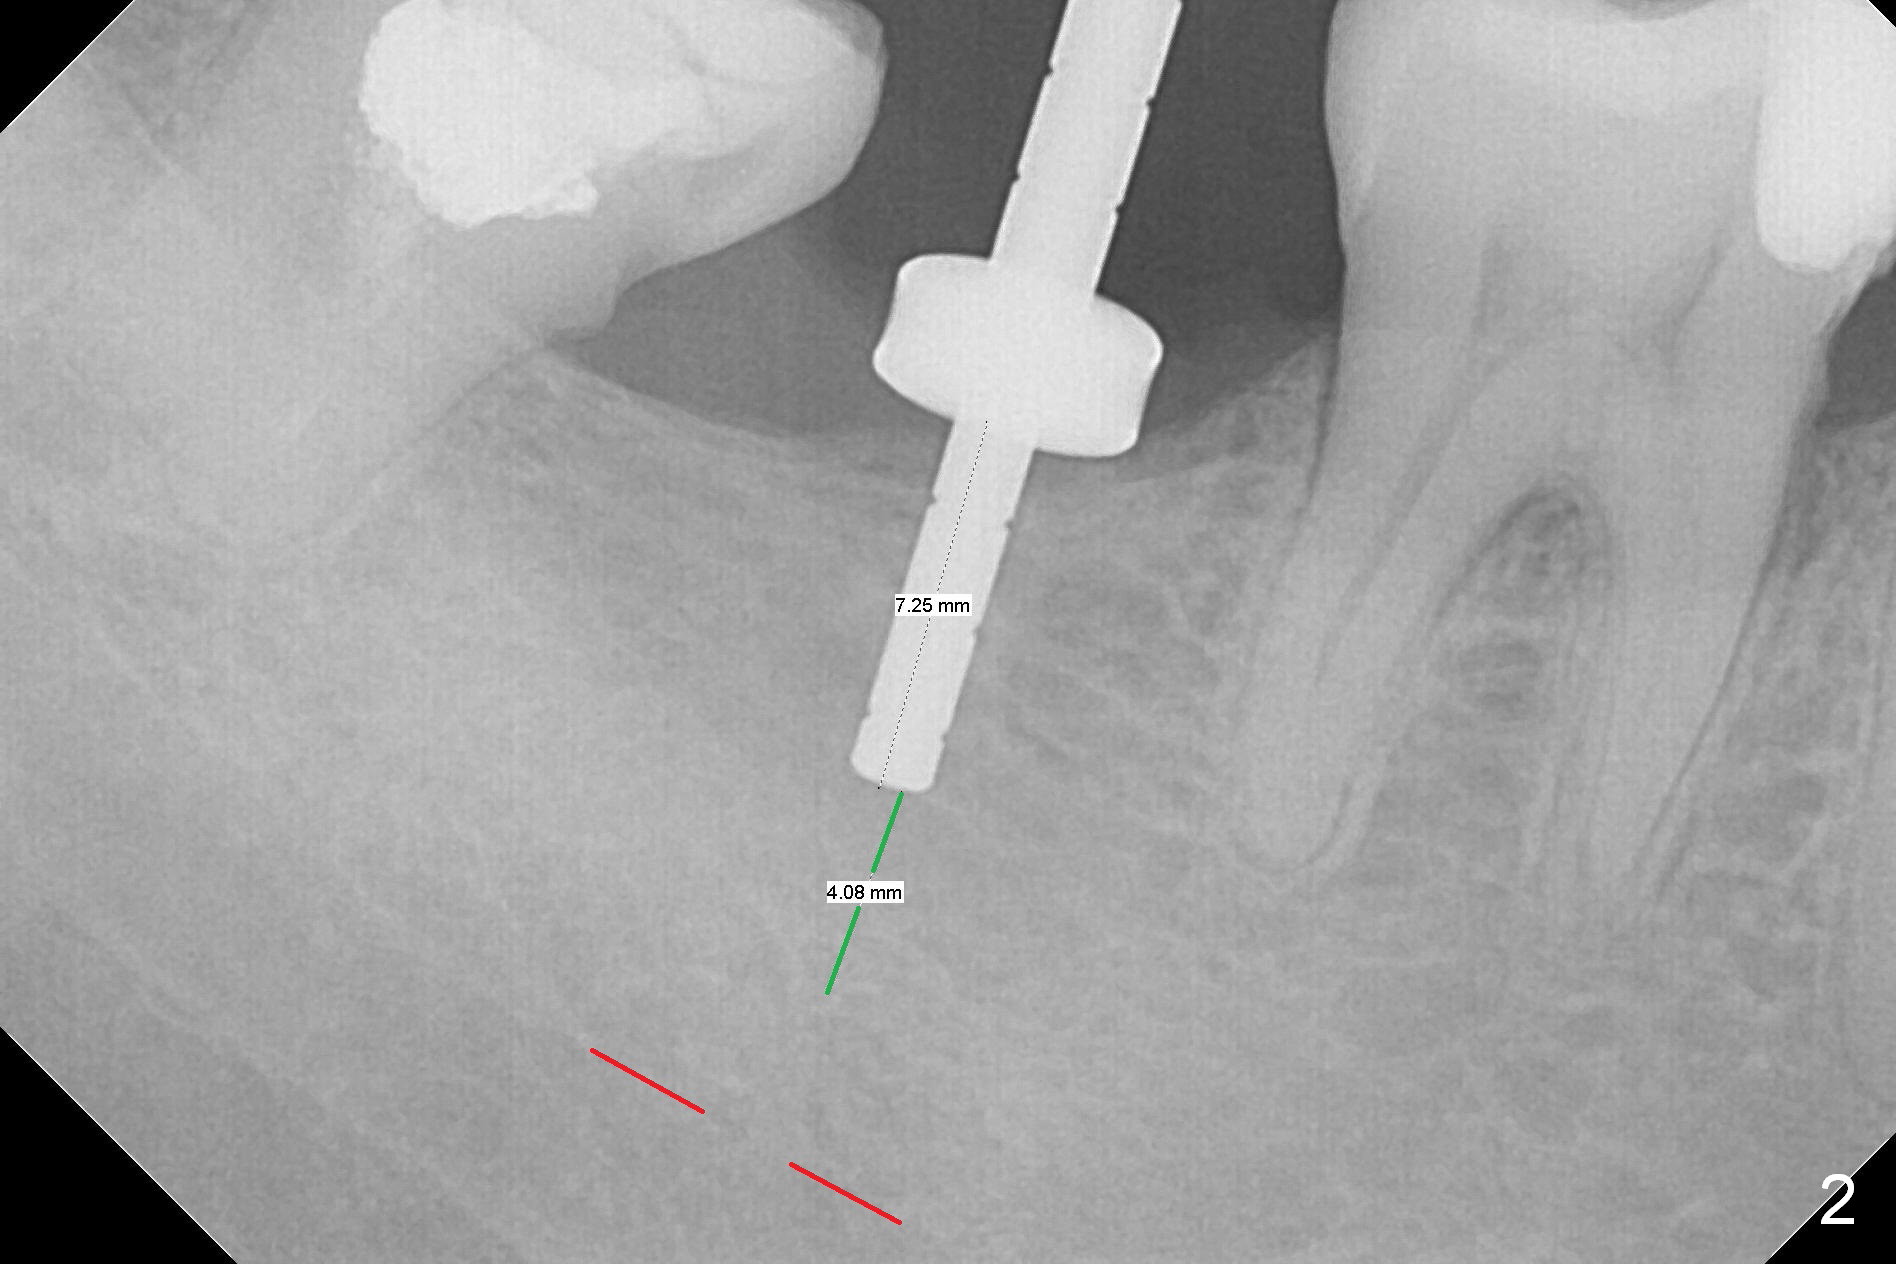

The ridge at #31 is also narrow buccolingually (Fig.1 *).  After incision and 1.6 mm pilot drill, a guide pin with 7 mm length is inserted to confirm trajectory and depth; it appears that 11 mm osteotomy has enough clearance from the superior border of the Inferior Alveolar Canal (IAC, Fig.2 red dashed line).  Following Marking Bur, 3.3 mm Magic Drill and final drill, the buccal plate seems to be thin (Fig.3 *).  When a 4x11 mm IBS implant and 5x4(2) mm pair abutment are placed, the distal thread is exposed (Fig.4 >), the abutment contacts the opposing tooth (data not shown) and there is 2.7 mm clearance from IAC.  After increasing the osteotomy 1-2 mm, the implant is placed deeper; the autogenous bone with Osteogen is placed around the plateau of the implant (Fig.5 >), particularly buccally, followed by collagen membrane.  When sutures are placed around the abutment, the buccal ridge looks bulkier (Fig.6) than preop (Fig.1).  It may remains so long term.  The flap surgery makes it possible for simultaneous GBR and reduction in possibility of peri-implantitis.  Last, periodontal dressing is applied.